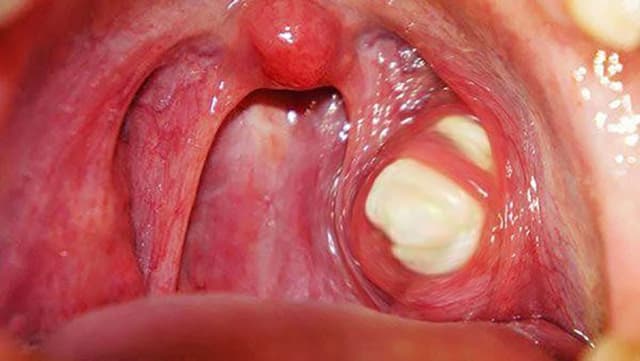

Những điều cần biết về bệnh viêm họng liên cầu khuẩn ở trẻ

Bệnh viêm họng liên cầu khuẩn thường gặp ở trẻ nhỏ, có thể dẫn tới các biến chứng nguy hiểm nếu trẻ không được điều trị sớm và khoa học. Hãy cùng tìm hiểu chí tiết hơn về viêm họng do liên cầu khuẩn và cách điều trị, phòng ngừa cho trẻ ngay sau đây. […]